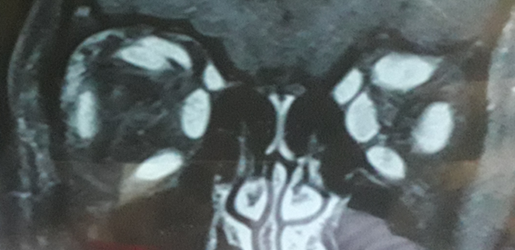

A 24.2 computerized visual field was performed without altered sensitivity in both eyes (Figure 1). An optical coherence tomography of the nerve fiber layer was also performed, which showed a borderline alteration of the upper NFL of the right eye (Figure 2), and a nuclear magnetic resonance where a diffuse thickening of the muscles can be observed. extraocular of both eyes without affectation of the tendon insertions (Figure 3). A basic laboratory was performed (complete blood count, coagulogram, glycemia, urea, creatinine, ionogram, erythrocyte sedimentation rate, PCR) to which was added thyroid profile with TRAB and ATPO antibodies, electrophoretic proteinogram, total antibodies, complete rheumatological profile, IgG4, serologies, radiography. chest and PPD with negative results. Having also ruled out possible myasthenia gravis. The only positive result was an IgE in values ​​that oscillated in each control at 1600 U/ml, remaining high in each laboratory control (Figure 4 & 5).

Figure 3 MRI without contrast: Diffuse thickening of the muscular bodies of the recti of both eyes is observed, including the levator palpebrae superioris muscle of the RE, causing the clinically evidenced ptosis.